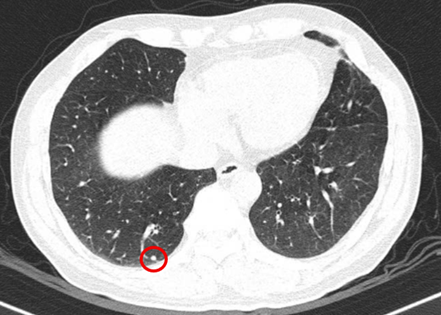

– Chụp cắt lớp vi tính ngực (11/07/2025) – trước phẫu thuật:

Hình 3: Hình ảnh chụp cắt lớp vi tính lồng ngực: Hình ảnh các nốt đặc rải rác 2 bên phổi, nốt lớn nhất kích thước 4mm (vòng tròn đỏ).

– Chụp cắt lớp vi tính ngực (06/08/2025) – sau phẫu thuật:

Hình 4: Hình ảnh chụp cắt lớp vi tính lồng ngực: Hình ảnh các nốt đặc rải rác 2 bên phổi, nốt lớn nhất kích thước 4mm (vòng tròn đỏ).